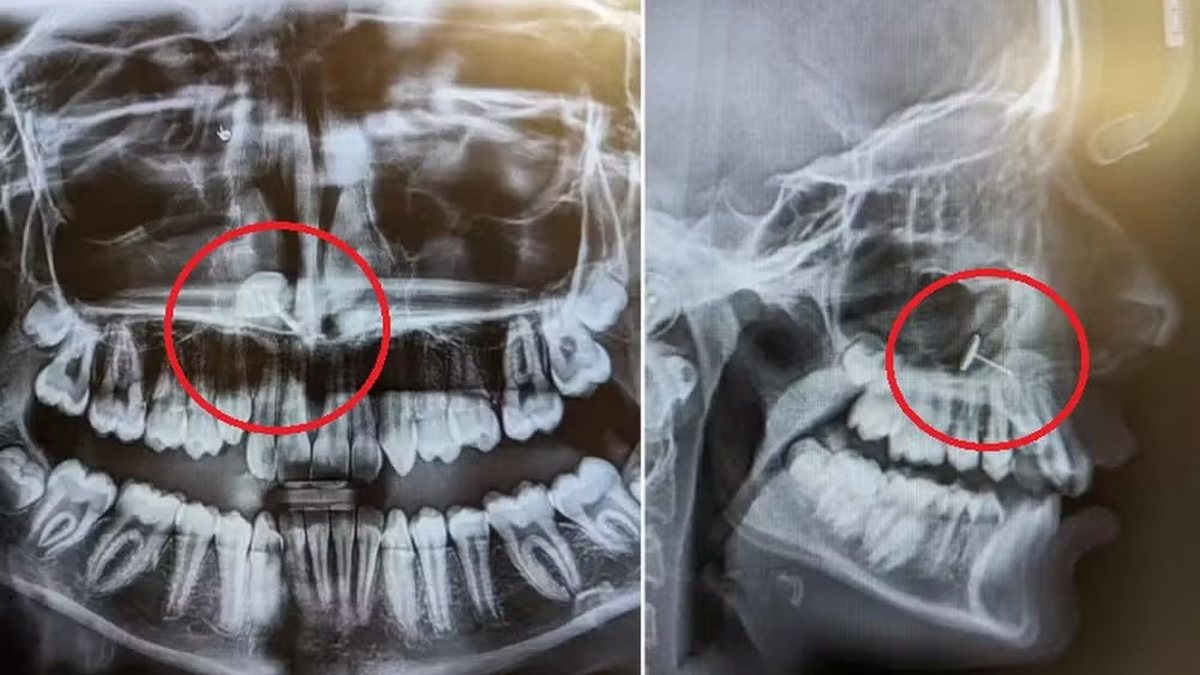

Uma ida de rotina ao dentista tomou um rumo inesperado para uma mãe e filha no estado de Washington (EUA). Quando a mãe levou a filha de 13 anos ao ortodontista para "iniciar o processo de colocação de aparelho", ela nunca poderia ter previsto o que veria em um raio X da boca de sua filha. "O ortodontista voltou para a sala e colocou o raio X na tela", contou ela à Newsweek. "Todos nós vimos ao mesmo tempo e passamos vários minutos tentando descobrir o que estávamos vendo", conta.

Parecia ser um pequeno pedaço de metal alojado nos seios nasais da menina. A mãe não conseguia explicar como aquilo tinha ido parar ali, mas uma pessoa na sala sabia exatamente o que tinha acontecido: sua filha. Para entender como chegaram a esse ponto, é preciso voltar seis meses, para quando a menina, que tinha acabado de completar 13 anos, perguntou à mãe se poderia "furar" o nariz.

Foi assim que as coisas continuaram até aquela fatídica ida ao ortodontista e o raio-X que revelou tudo. A mãe compartilhou as imagens em sua conta do Reddit, onde rapidamente se popularizaram, recebendo mais de 73 mil curtidas. A boa notícia é que a história teve um final feliz e totalmente indolor. "Assim que descobrimos o que era e como tinha chegado lá, liguei para o otorrinolaringologista que havia removido as amígdalas dela alguns anos antes e ele conseguiu removê-las com uma pinça médica muito longa e mão firme", disse a mãe.